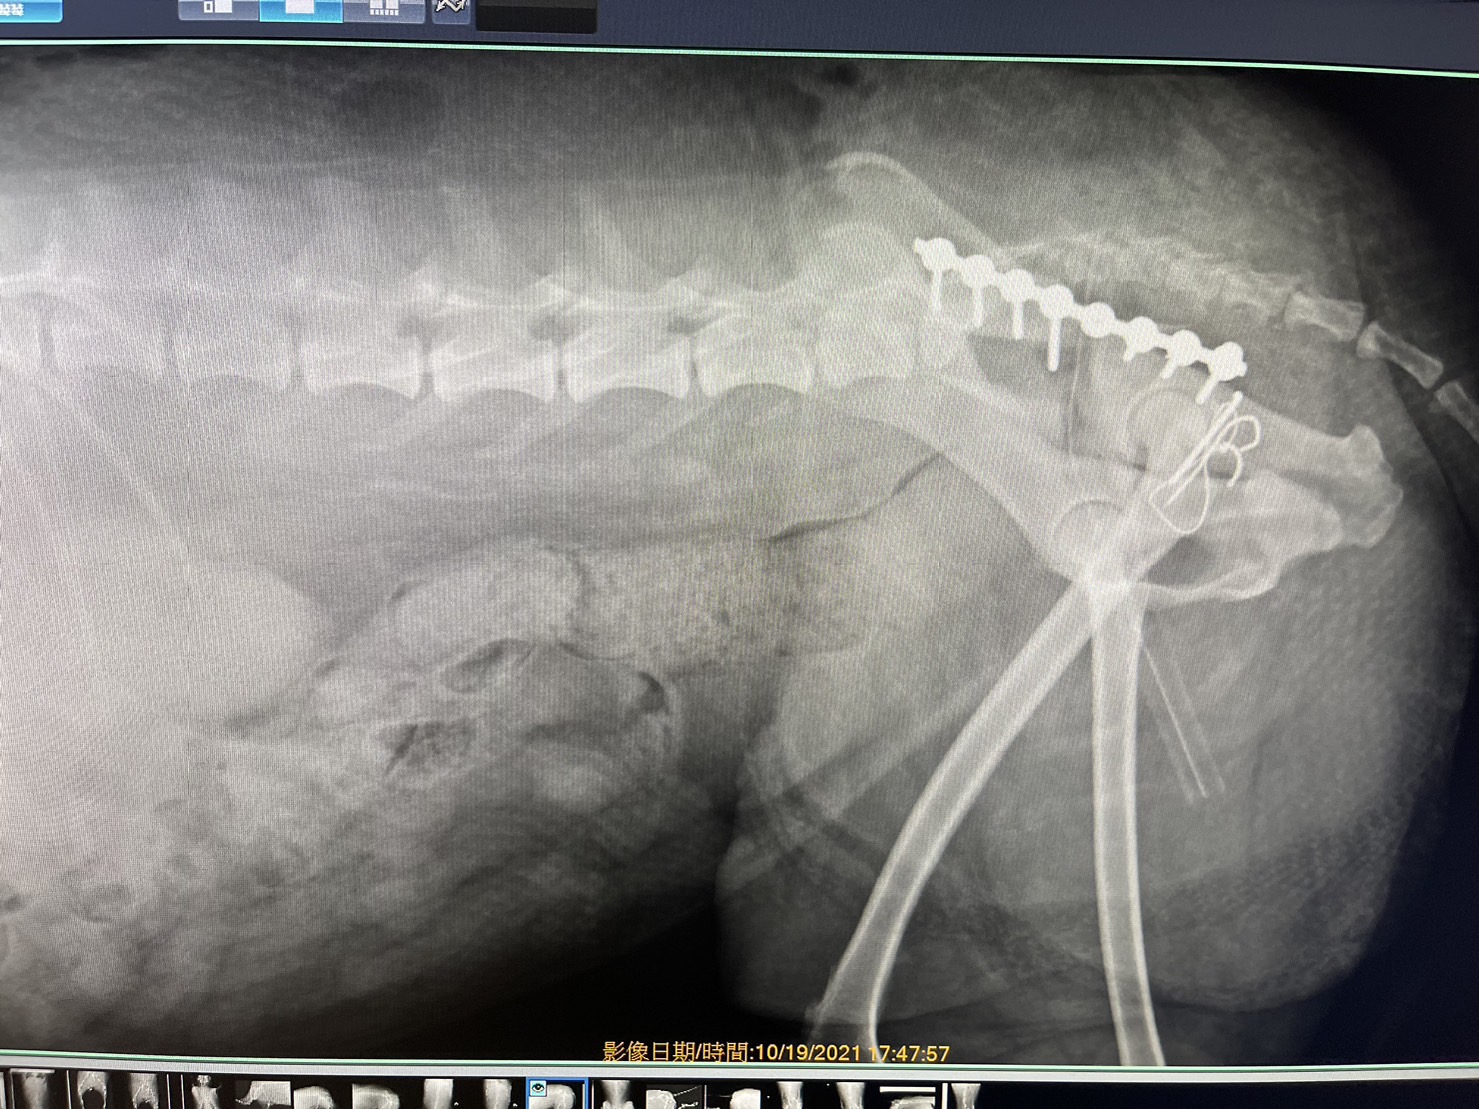

狗狗 車禍 骨盆骨折

狗狗的骨盆骨折相對於常見的四肢骨折 不容易單純靠xray 診斷及擬定手術計畫藉由電腦斷層影像的支援 能提高手術成功的機率

14kg 11歲的莓莓 術後10個月追蹤 行動自如一切正常喔

術前

術後

電腦斷層影像